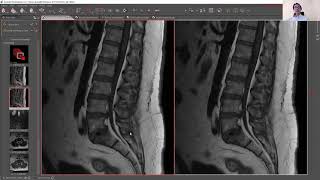

Discopatia, aracnoidite, cisto sinovial... como avaliar na prática alterações de coluna da rotina

1:02:51

Discopatia, aracnoidite, cisto sinovial......

NEUROIMAGEM NA PRÁTICA - Fabio Takeda

9,127 views